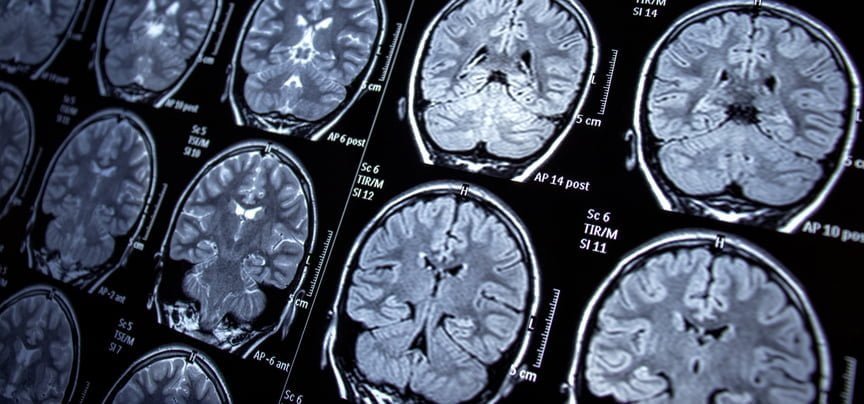

El estudio prequirúrgico del RNS toma hasta un año, incluyendo una estadía de dos semanas en la UEM para monitorear la actividad cerebral a través de unos 15 electrodos implantados para determinar el área precisa del cerebro involucrada en las convulsiones del paciente, dijo el Dr. Khaled.